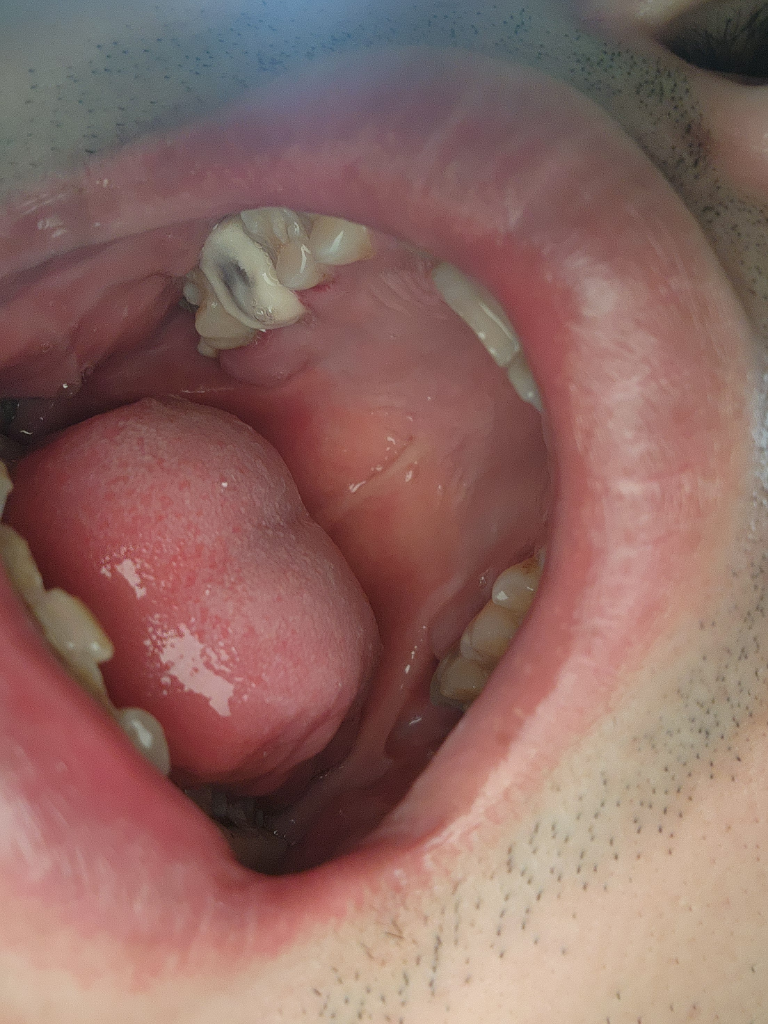

임시치아 상태이신거 같은데 임시치아 상태는 너무 딱딲하거나 질긴음식은 피해주시고, 말그대로 임시로 붙혀 놓은거니 잘 떨어질수 잇으 주의 하시는게 좋습니다.

임시치아는 보철물보다 강도가 약하고 잘 탈락할 수 있기 때문에 그 이전까지 부드러운 음식을 먹는 것이 좋습니다. 또한 너무 끈적끈걸 먹을 수 있으면 탈락할 수 있기 때문에 너무 끈적한 음식을 드시지 않는 것이 좋습니다. 흡연을 하는 것은 임시 치아와는 큰 영향이 없습니다.

해당 부위 딱딱하거나 질긴 음식만 주의하면 되겠습니다. 음주나 흡연은 임시치아와 크게 상관은 없습니다. 다만, 음주와 흡연은 모두 치아와 잇몸에 좋지 않습니다.